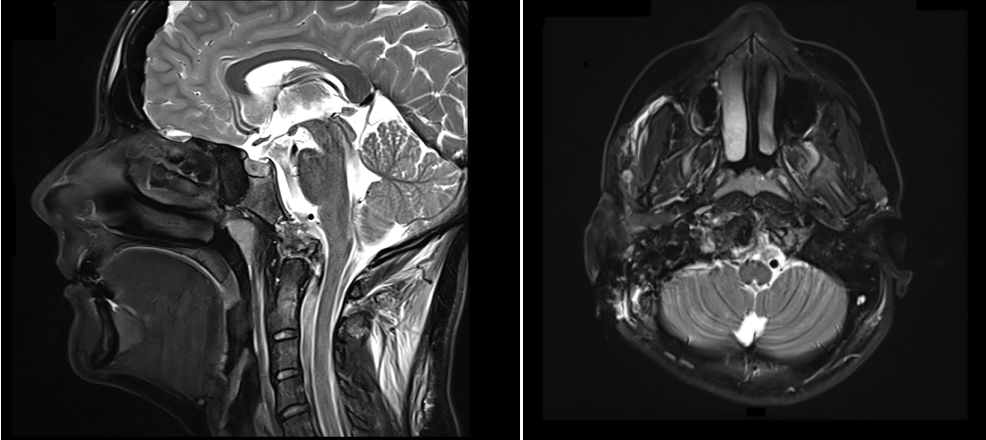

颅颈交界区脊索瘤是“国际疑难”手术之一,特别是当肿瘤侵犯到硬膜内和脑组织、神经血管黏连时。21岁女孩,因颈部疼痛做MRI检查发现脊索瘤,在颅颈交界区、枕骨大孔内呈侵袭性生长,累及双侧椎动脉,硬膜内侵犯,手术风险较大,曾一度治疗无望。

术前MRI

福洛里希教授运用高超的手术技术,使用前外侧入路并以进入颅颈交界区,顺利地切除肿瘤。内镜通过相对狭窄的硬脑膜开口提供宽视角,可以帮助硬脑膜内肿瘤切除(图2)。实现了肉眼全切除,术后过程很顺利,无新发神经功能缺损。术后MRI也证实了在没有并发症的情况下实现了全切。总之,内镜辅助下的前外侧入路可为颅颈交界区脊索瘤的手术治疗提供顺利合适的通道。

图1,术前和术后磁共振成像(MRI)。(A)术前矢状面t2加权MRI显示以颅颈交界区为中心的高信号病变(脊索瘤),伴有硬膜内延伸和神经血管结构受压。(B)术后矢状T2加权MRI显示肿瘤实现了全切。

术后MRI证实了在没有并发症的情况下实现了全切